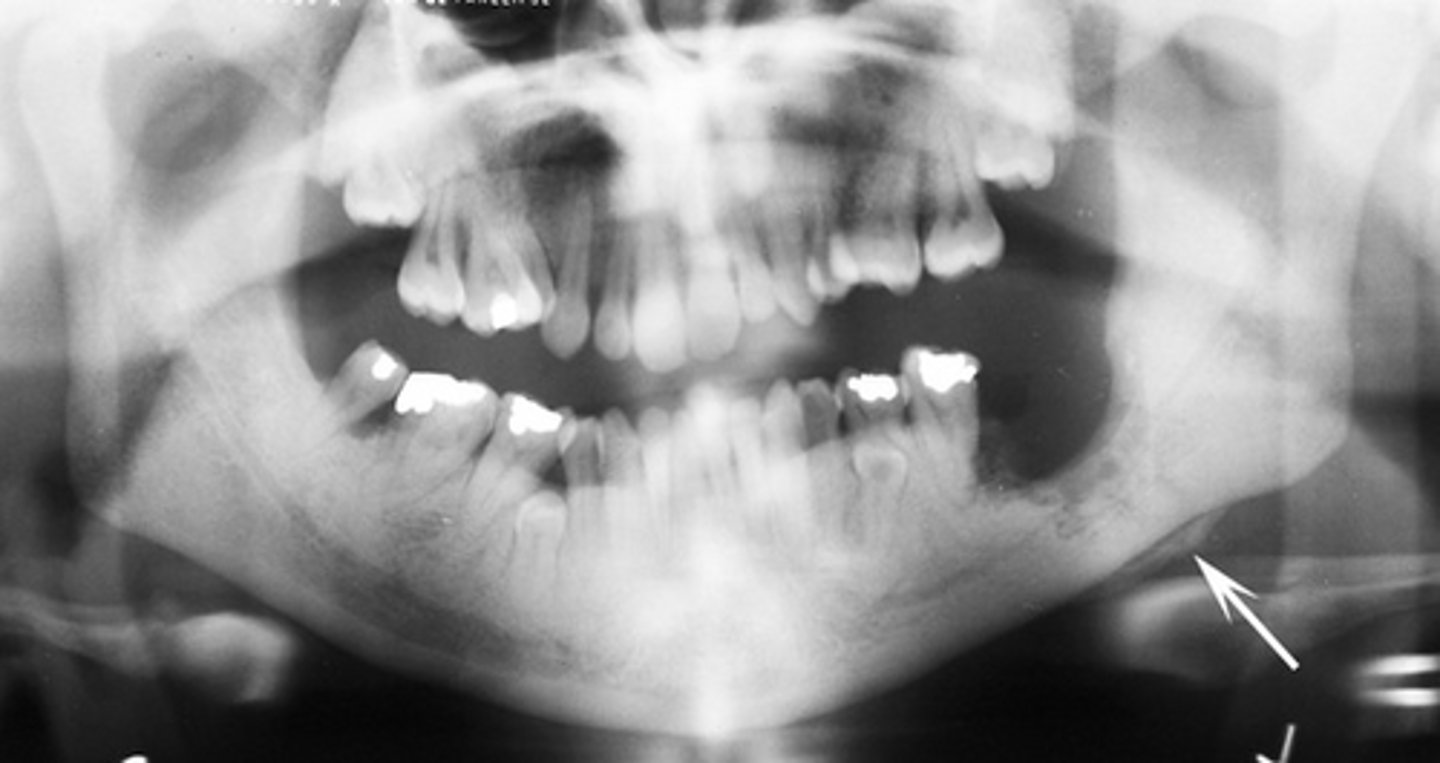

Root tip dislodged into the maxillary sinus.

You can see the PDL

How can you differentiate this from an antroliths in the maxillary sinus?

Root fragment dislodged into the maxillary sinus, this has implications for maxillary posterior extractions.

What does the image show?